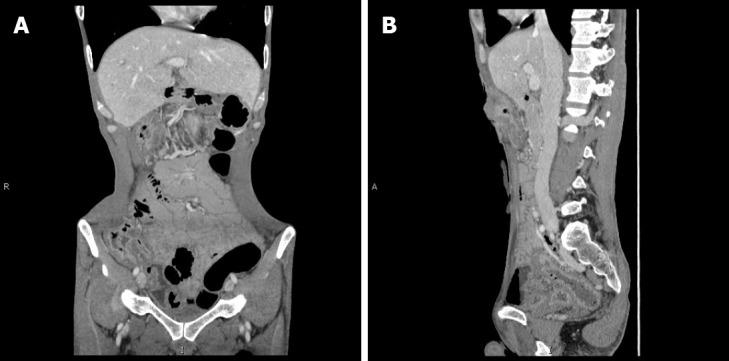

This case report refers to a 40-year-old male with a 6-year history of CD. The patient underwent transverse colostomy because of inflammatory ileus in 2017. He subsequently received infliximab treatment in 2018. Ten months later, worsening contracture of the transverse colostomy was observed. Imaging tests indicated that the patient may have developed colon cancer with extensive peritoneal implantation. At the same time, colonoscopy revealed a rectal mass and pathological examination indicated well-differentiated adenocarcinoma. Palliative ileostomy was performed to improve defecation in 2019. During the operation, a small nodular mass in the mesentery of the small intestine was identified and pathological examination of the mass revealed advanced adenocarcinoma. The patient was diagnosed with advanced colorectal cancer and administered palliative chemotherapy. He died in June 2020.

本病例报告涉及一名有6年CD病史的40岁男性。该患者因2017年的炎性肠梗阻接受了横结肠造口术。他随后在2018年接受了英夫利昔单抗治疗。十个月后,观察到横结肠造口术挛缩加重。影像学检查表明患者可能已发展为伴有广泛腹膜种植的结肠癌。同时,结肠镜检查发现直肠肿物,病理检查显示为高分化腺癌。2019年进行了姑息性回肠造口术以改善排便。手术期间,在小肠系膜中发现一个小结节状肿物,肿物的病理检查显示为晚期腺癌。该患者被诊断为晚期结直肠癌并接受了姑息化疗。他于2020年6月去世。